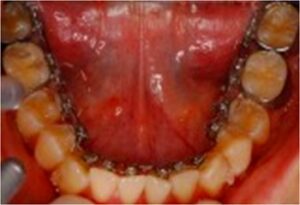

無料メール相談5(見えない矯正方法ってどんなのがありますか?)

今まで、多くの方々に無料でメール相談をしてきました。その中から良くある相談を紹介しています。 「接客業をしているので、矯正の装置が見えないようにして矯正したいので、期間と費用を教えてください。」 とても、よくある質問ですが、一概に治療期間は […] 本文を読む